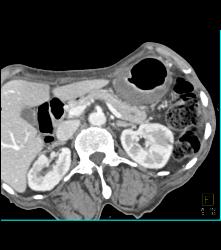

Antral Carcinoma With Peritoneal Tumor Implants